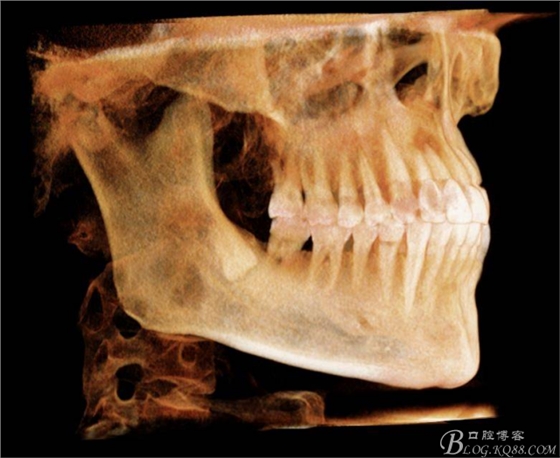

圖5. 48的三維視圖